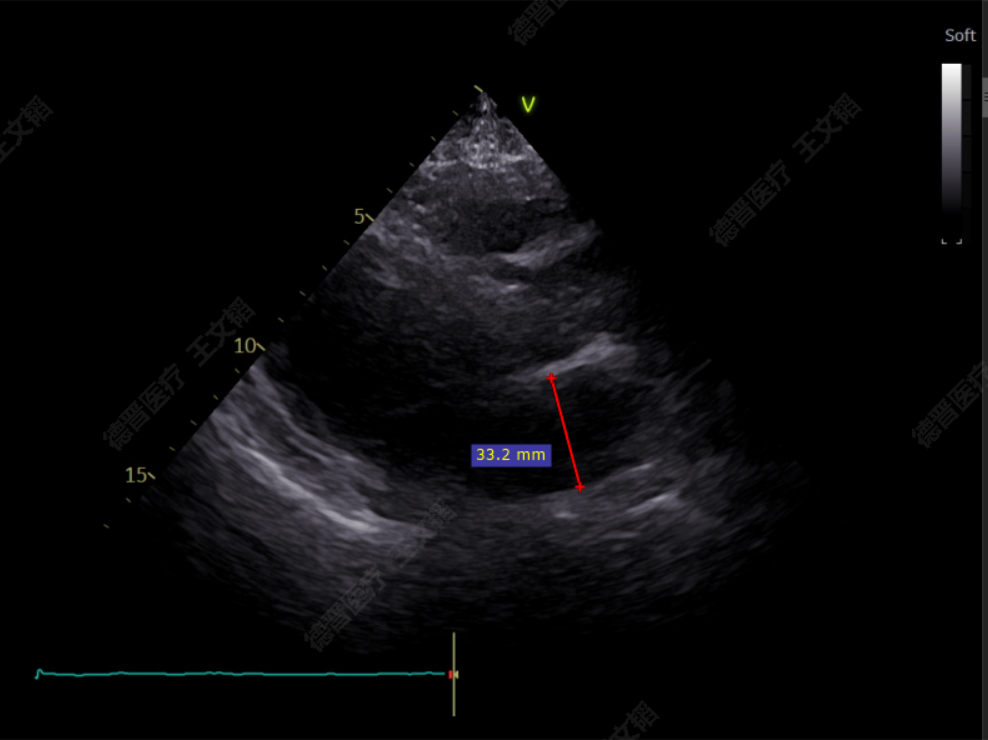

患者为73岁老年男性,经食道超声检查提示:急性二尖瓣腱索断裂合并反流,前叶长度:2.8cm,后叶长度:1.7cm,脱垂宽度:18mm,脱垂高度:8mm,瓣口面积:6.5cm²。

左房极小

房间隔增厚